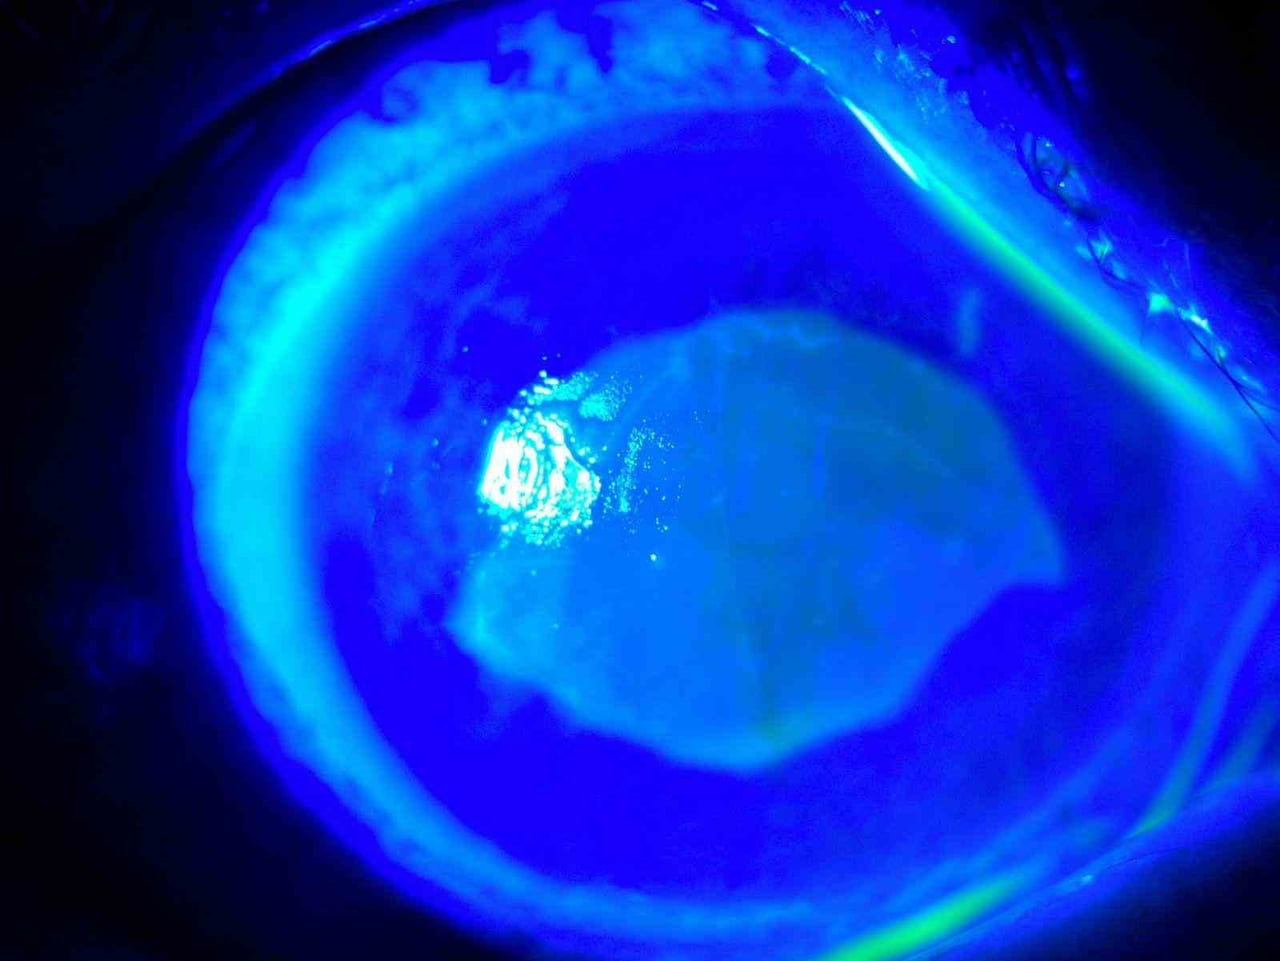

Hastanın tedavi öncesindeki göz fotoğraflarında göz bebeğinin beyazlaşması ve göz akının kızarıklığı kayıt altına alındı; Doç. Dr. Yılmaz, erken başvuru ve uygun tedavinin görsel sonuçta belirleyici olduğunu belirtti.